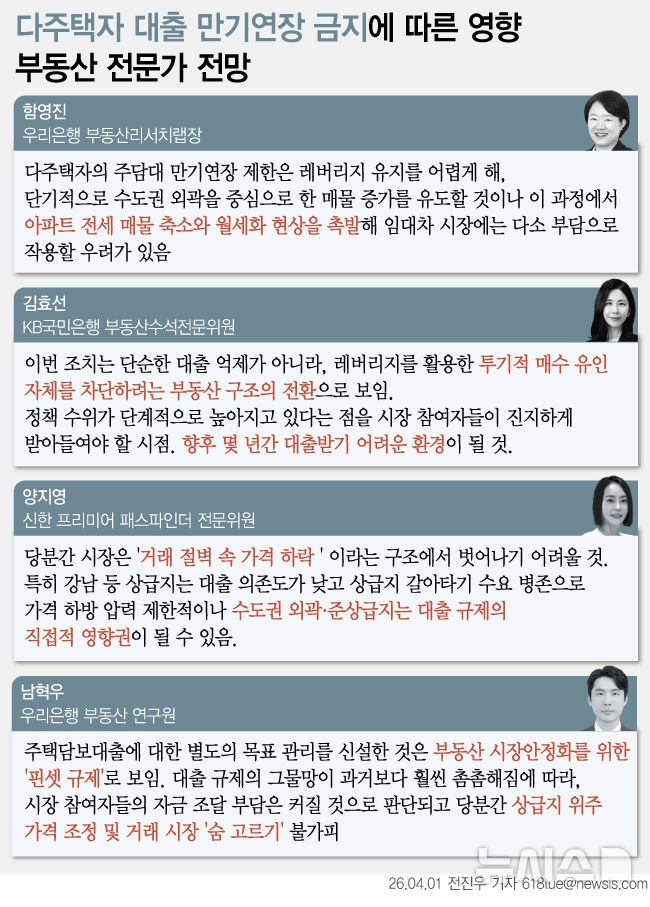

연구에는 일반 이미지로 학습된 모델(OpenCLIP, DINOv2)과 의료 영상으로 학습된 모델(CheXagent, RAD-DINO) 등 네 가지 모델이 사용됐다. ▲마지막 분류 단계만 새로 학습하는 '선형 검증' ▲모델의 일부 레이어만 재학습하는 '부분 미세조정 방식' ▲저차원 행렬을 추가하는 'LoRA 방식' 등 세 가지 방법을 적용해 총 12개의 AI 모델을 만들었다.

또 의료 영상 기반 모델이 항상 더 우수한 것은 아니며, 예측 성능이 높다고 해서 설명 가능성까지 함께 향상되는 것은 아니라는 점도 확인됐다. 이는 의료 AI가 실제 임상에서 활용되기 위해서는 정확도와 함께 ‘왜 그렇게 판단했는지’에 대한 근거 검증이 필수적임을 보여준다.

제1저자인 김재원 연구원(서울대 의과학과)은 "파운데이션 모델을 의료 영상에 적용할 때는 높은 성능만으로는 충분하지 않고, 실제 의료 현장에서 신뢰받기 위한 다차원적 평가 체계가 필요하다"며 "이번 연구가 그 기준을 제시했다는 점에서 의미가 크다"고 설명했다.

교신저자인 박상민 교수(가정의학과)는 "예측 정확도뿐 아니라 AI의 판단 근거를 투명하게 설명할 수 있는지를 함께 평가해 파운데이션 모델을 어떻게 선택하고 활용해야 하는지에 대한 방향성을 제시했다는 점에서 큰 의의가 있다"고 말했다.